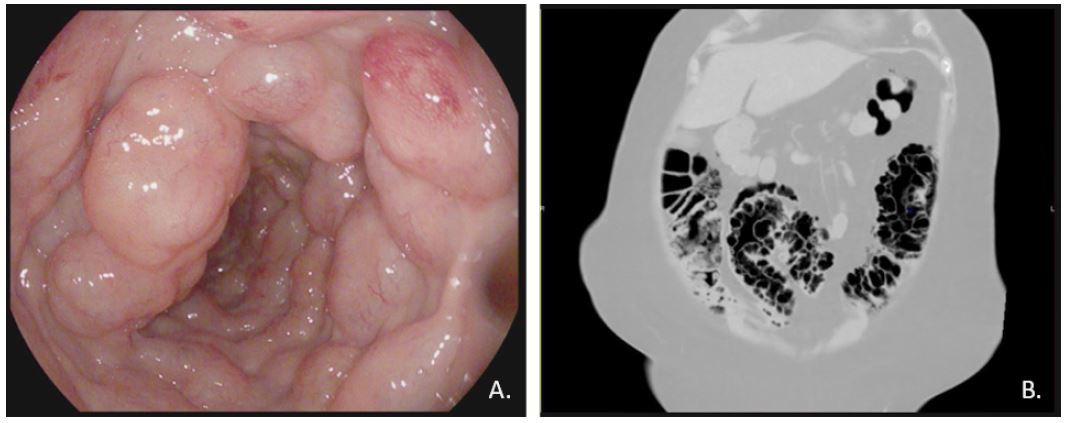

As a part of a thorough evaluation, a colonoscopy was performed, revealing gas-filled cysts from the sigmoid colon to the right colon. A subsequent abdominal CT scan confirmed pneumatosis intestinalis extending from the right colon to the sigmoid colon, along with pneumoperitoneum. The patient was treated with an elemental diet and metronidazole for 8 days [1].

Figure 1: (A) Endoscopic features: polypoids, gas-filled cysts in the lumen of the colon.

(B) Computed tomography showing extensive pneumatosis of the colon and pneumoperitoneum.